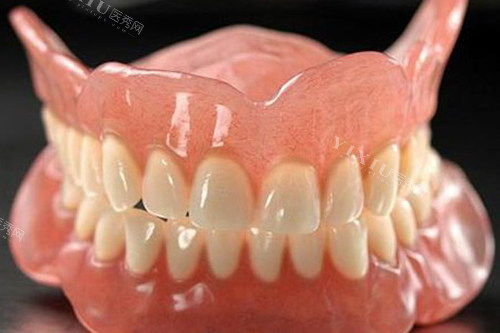

给老爷子看牙的是一位经验充足的医生,姓王。王医生特别有耐心,先是仔细地检查了老爷子口腔的情况,然后又问了问老爷子平时的身体状况和饮食习惯。接着,他跟我们详细地介绍了几种适合老爷子的假牙类型,什么活动假牙、固定假牙,每种假牙的优缺点、价格都讲得明明白白。

我们本来是倾向于活动假牙的,觉得方便清洁。但是王医生根据老爷子的口腔条件,建议我们选择固定假牙。他说老爷子的基牙条件还不错,固定假牙戴上之后更舒服,咀嚼功能也更好,虽然价格会高一些,但长远来看更合适。听了王医生的分析,我们觉得挺有道理,就决定听他的建议。

接下来就是制作假牙的过程了。医院的工作人员安排得很妥当,给老爷子取了牙模,还让我们留下联系方式,说做好了会头一时间通知我们。大概过了一周左右,我们就接到了医院的电话。再次来到医院,王医生亲自给老爷子安装假牙。安装的过程中,他不断地询问老爷子的感受,调整假牙的位置,确保老爷子戴着舒服。

安装好之后,老爷子试着咬了咬东西,脸上立马露出了笑容,说感觉好多了,吃东西也不费劲了。我看着老爷子开心的样子,心里也踏实了。而且,医院还跟我们说了一些假牙的保养方法,让我们有什么问题随时联系他们。